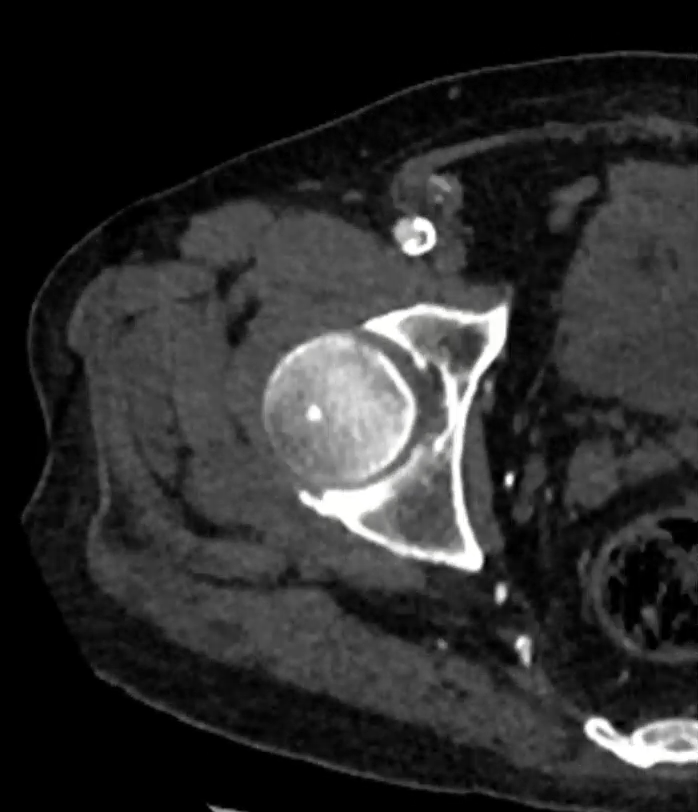

术中,团队首先使用开通导丝突破重度钙化病变,然后用2.0、2.5、3.0*150mm普通球囊逐级预扩张。造影显示血流较前稍改善,但钙化病变处仍有严重残余狭窄。

随后使用LiqMagic?P18外周血管内冲击波导管进行钙化斑块的压裂。根据血管尺寸,团队选择了4.0*60mm和5.0*60mm两个规格在4atm压力下逐段扩张整段病变,共进行了6个周期的冲击波治疗,将冲击波球囊加压至12atm显示病变狭窄解除,均匀扩开,保压1min后造影结果显示血流恢复通畅,钙化部位的残余狭窄明显改善。

▲4*60冲击波球囊扩张